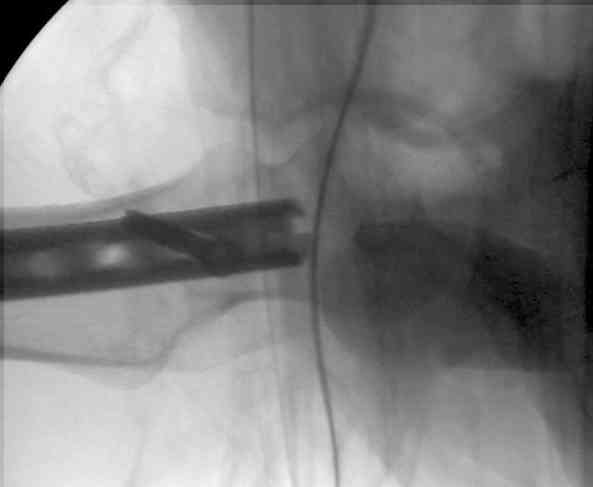

Учитывая, что ложный сустав с укорочением, для восстановления необходимо применение дистракции (на кольцах или femoral distractor) или другой методикой, например после определения длины, штифт вводят в канал, не снимая Insertion tool, блокируется дистально шурупами и дальше штифт доводится до желаемого положения, затем через jig

производят блокировку проксимально